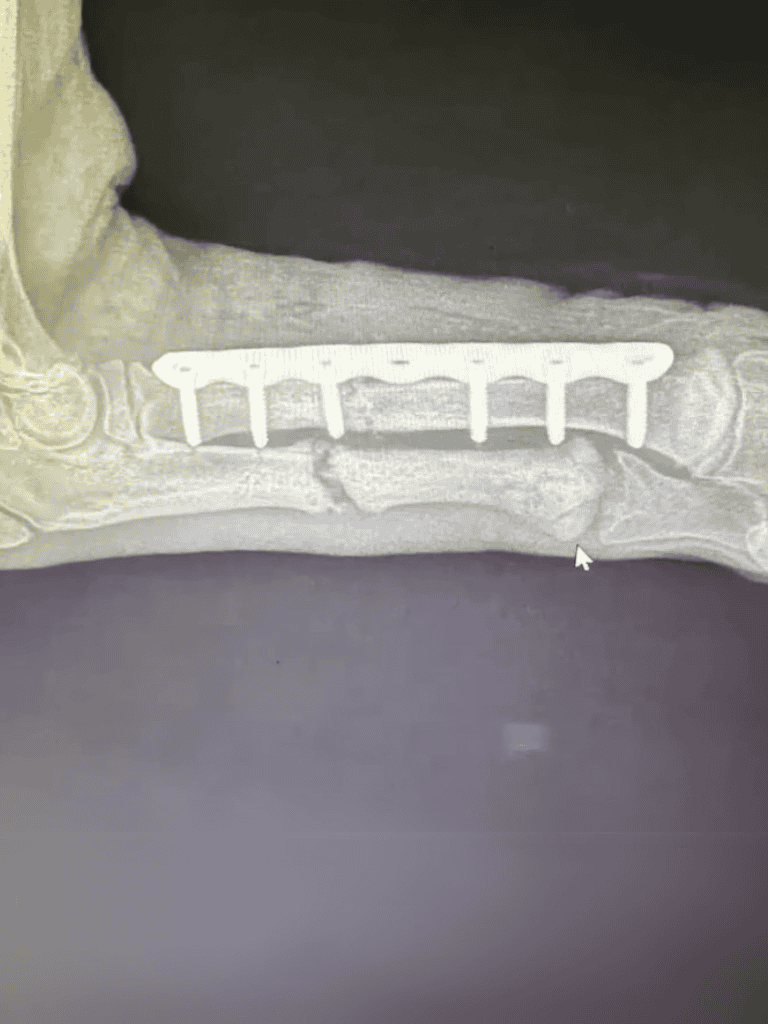

As the vets carefully examined the little pup, they noticed troubling signs. Fresh bruises hinted at more suffering endured in recent days. It was clear that swift surgical intervention was necessary to save his life.

What started as a minor fracture quickly became a dire situation as the puppy’s leg developed a severe infection. This little fighter endured a grueling three-hour surgery to combat the aggressive spread of the infection.